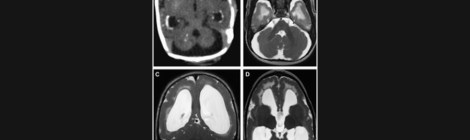

Guest Post by Dr. Manuel Casanova: “Enlargement of the Brain Ventricles in Preterm Infants and Autism: An Ultrasound Study”

Our latest research, click the image for the original paper